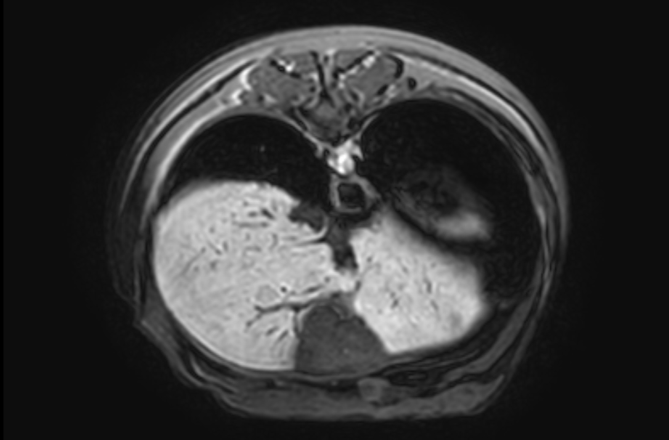

04복부 MRI

· 간, 골반강 평가

03복부 CT

· 간, 비장의 종양을 포함한 실질 변화 및 혈관기형(PSS)의 평가

· 소화기, 비뇨기 실질장기의 평가(종양, 이물, 염증 등)